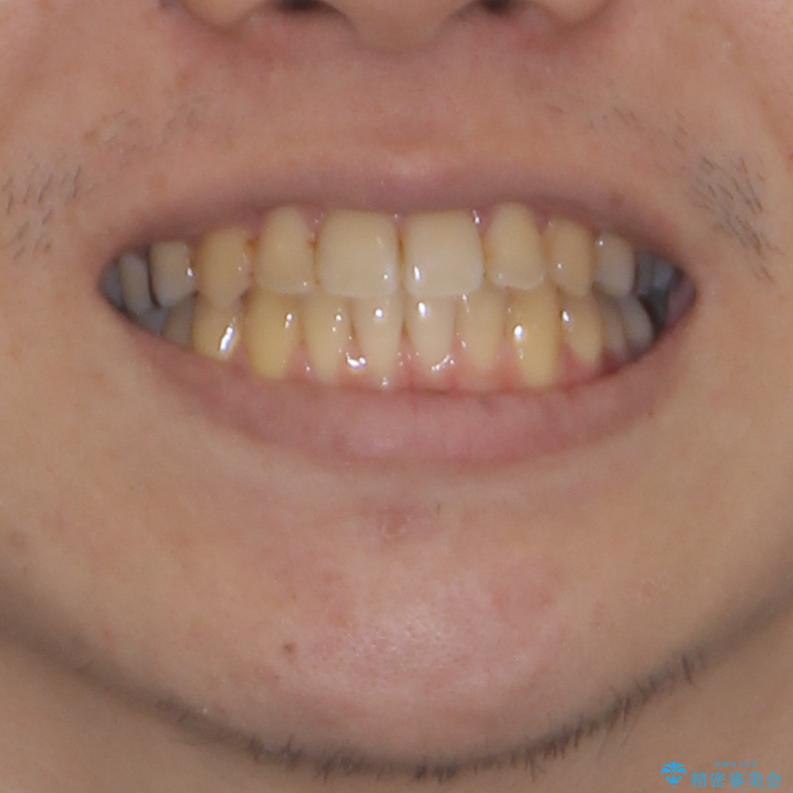

前歯のクロスバイトをインビザラインで矯正治療

- 前歯のデコボコとクロスバイトを気にして来院された患者様です。

前歯を早く整えたいとの希望があったので、ワイヤー矯正にて短期間でクロスバイトを解消し、その後インビザラインにて整えることとしました。